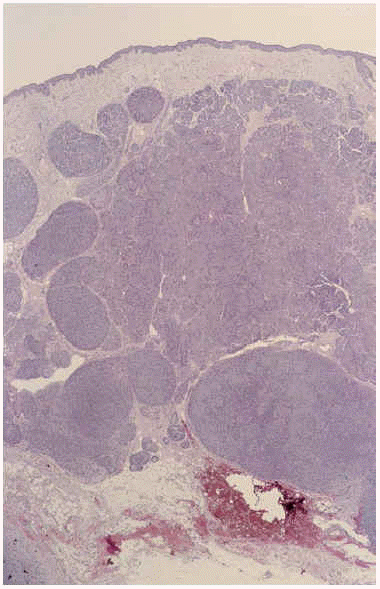

El estudio histológico de la lesión preauricular mostraba una neoformación de células basaloides, sin conexión epidérmica, en cuya porción inferior había grandes lóbulos redondeados, mientras que en su porción superior los lobulillos estaban agregados «en rompecabezas» (fig. 2) con formación de conductos y membrana basal prominente (fig. 3). Los grandes nódulos profundos mostraban una sábana de pequeñas células de núcleo muy teñido, salpicada de luces tapizadas por células mayores y más claras. En los intersticios había material hialino (fig. 4). Se trataba, por tanto, de una mezcla de los patrones del cilindroma (arriba) y espiradenoma (abajo).

Fig. 2.--Extirpacion de la lesión tumoral que muestra en su porción inferior grandes lóbulos tumorales redondeados, mientras que en su porción superior hay pequeños lobulillos agregados «en rompecabezas» (hematoxilina-eosina x100).